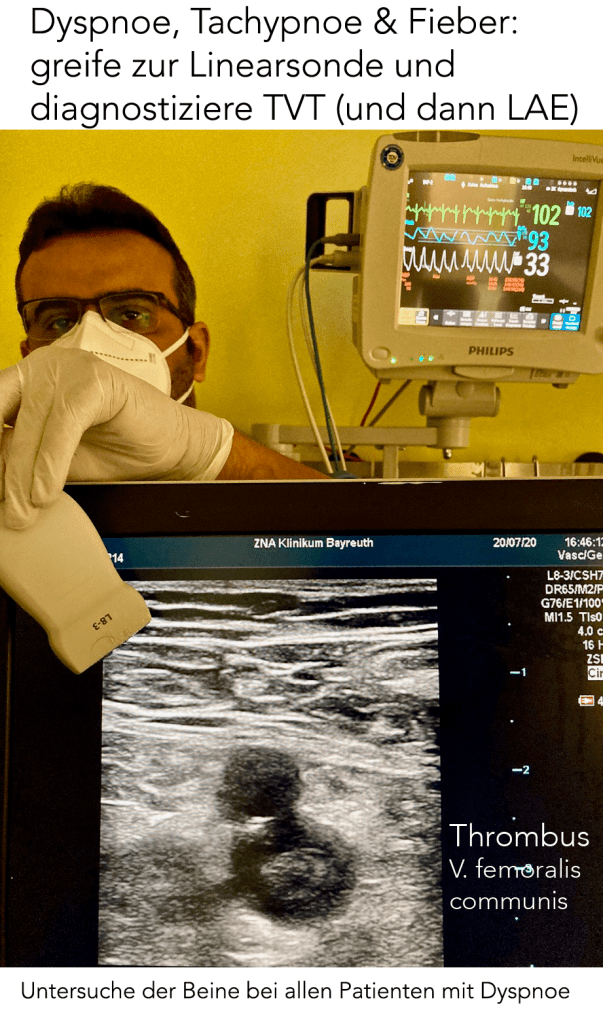

dyspnoe-fever-pe-thrombus-pearl-naji-text-de